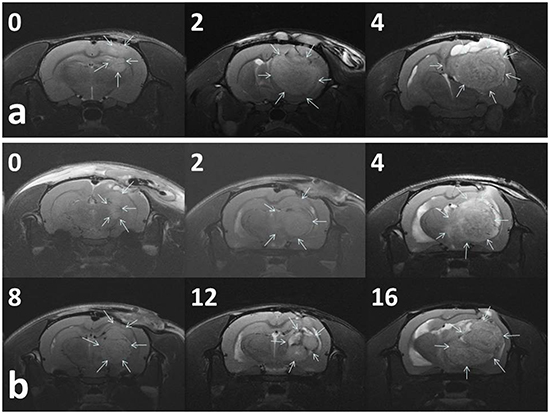

Figure 5a presents the serial MRI scans of the animals in the control group. The implanted tumour rapidly grew and resulted in an intense mass effect (midline shift and brain stem compression), eventually causing the rats to die. Figure 5b illustrates the serial brain MRI scans of the animals in the BIC group, in which the created tumour grew more slowly than in the animals in the control group. The tumour volumes decreased between Weeks 4 and 8 and thereafter progressively regrew and caused the death of the rats in Week 23. Figure 6 presents the serial brain MRI scans of the rats in the BIC group. The initial tumour volume (62.73 × 10−3 mL) was similar to the mean tumour volume in the control group (60.36 ± 38.69 × 10−3 mL). The tumour slowly grew and reached the maximum value in Week 4 and thereafter decreased steadily and nearly disappeared at the end of the study.

Figure 5: Serial MRI images in the control group A. and BIC group B. The number in the upper right corner of each image indicates the number of weeks after the implantation of nanofibrous membranes. a. The tumour volumes of most (93.33%) of the rats in the control group rapidly increased and resulted in a severe mass effect and death. b. The rats in the BIC group exhibited a partial response to BIC/PLGA nanofibrous membrane treatment, and the tumour volumes temporarily decreased between 4 and 12 weeks, followed by a rapid increase in the volume.